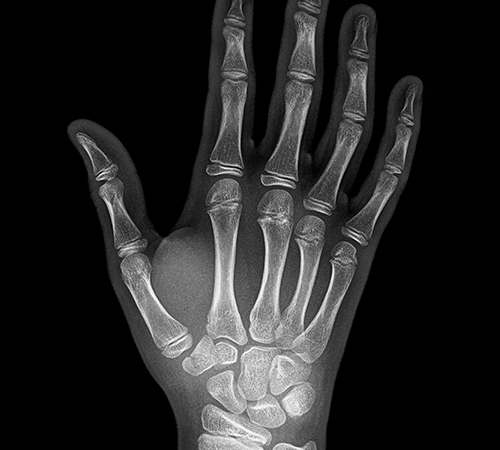

결정종

• 결정종

• 결정종 진단

결절종은 종양의 위치, 운동성, 촉진 시의 감촉 등으로 진단합니다. 혹 안에 주사기를 넣어

투명한 젤리처럼 생긴 끈끈한 액체를 뽑아내어 진단하기도 합니다.

이렇게 주사기로 액체를 뽑으면 혹이 없어지지만, 1~2일이 지나면 다시 혹이 커집니다.

따라서 이 방법은 치료 목적으로 사용하지 않습니다. 이외에 다른 요인으로 결절종이 발생할 수도 있어

방사선 사진, 초음파나 MRI 촬영을 진행하기도 합니다.